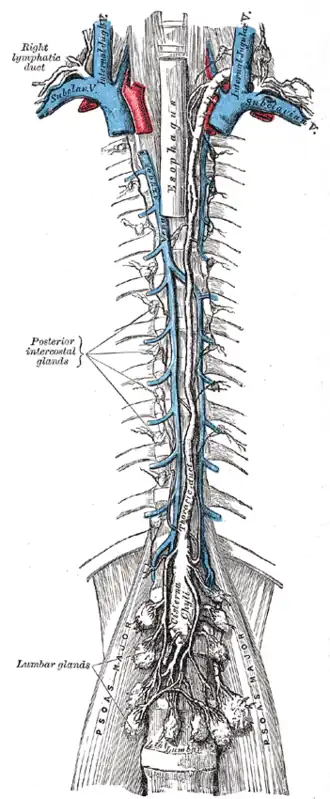

Cisterna chyli is the white bulb in the center near the bottom. | |

Modes of origin of thoracic duct. a. Thoracic duct. a’. Cisterna chyli. b, c’ Efferent trunks from lateral aortic glands. d. An efferent vessel which pierces the left crus of the diaphragm. e. f. Lateral aortic glands. h. Retroaortic glands. i. Intestinal trunk. j. Descending branch from intercostal lymphatics. | |